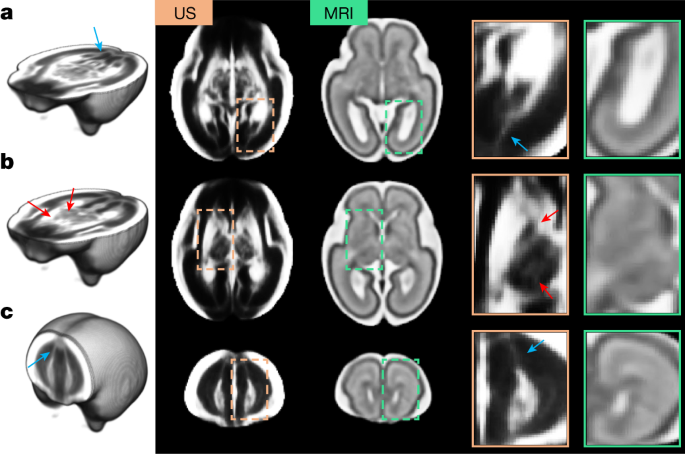

Our weekly atlas templates correspond to the structures visible from 21 to 31 weeks’ gestation in the Computational Radiology Laboratory (CRL) MRI-based atlas of human fetal brain maturation9. Owing to the unique characteristics of each modality’s physical interactions with brain tissue, a one-to-one intensity mapping between the 3D US and MRI modalities was not possible. Nevertheless, Fig. 2 shows that the tissue boundaries are visible and colocalize in the two modalities, and the shape and spatial extent of the structures are comparable in age-matched templates.

a–c, Age-matched templates shown at two axial views: level of the ventricles (a) and level of the thalami (b), and one coronal view (c). Structures colocalize in both modalities, but US templates showed sharper tissue boundaries in the subcortical grey matter areas (red arrows). Blue arrows indicate possible white matter fibre bundles in the US atlas, which are not visible in the MRI atlas. Note that the contrast of the US atlas has been edited to highlight the key structures.

Although the MRI atlas shows good separation between the subplate and intermediate zone, some structures are more clearly distinguished in the US versus magnetic resonance images: in particular, the boundaries separating the thalamic nuclei, putamen and internal capsule (Fig. 2b, red arrows) from the posterior lateral ventricle cavity (Fig. 2a). US also identified possible white matter fibre bundles (for example, forceps major from 18 weeks’ and minor from 24 weeks’ gestation, Extended Data Fig. 2) that are usually only visible in diffusion-weighted MRI sequences33,34 (Fig. 2a,c, blue arrows).